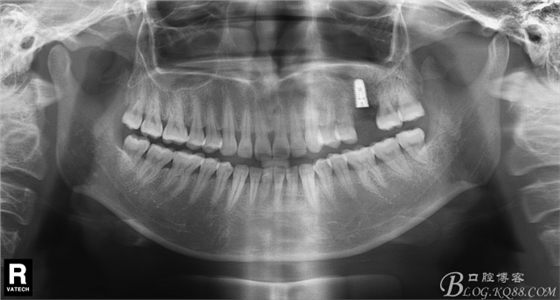

患者唐某某,男,50歲,要求種植修復(fù)左上缺失大牙。

術(shù)前X片。